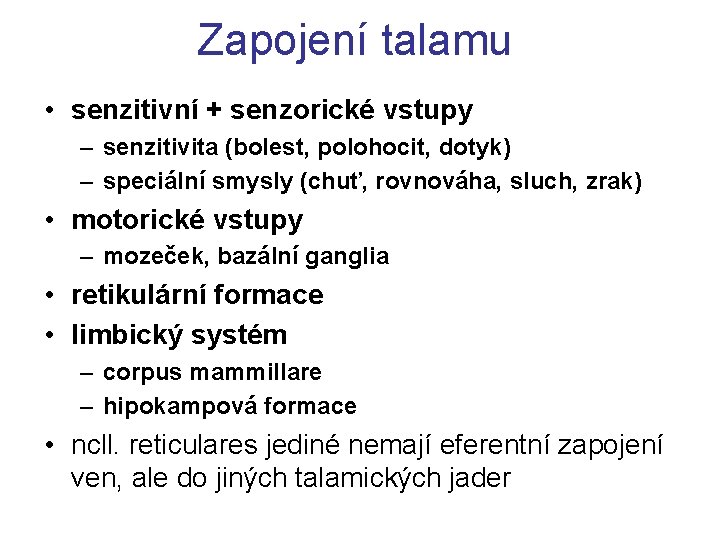

Spoje talamu AF: • senzitivní a senzorická – bolest, polohocit, hmat, chuť, rovnováha, sluch, zrak • motorická – mozeček, BG • RF - ARAS • limbický systém – corpus mammillare, hippocampus EF: mozková kůra + hypothalamus reciproční spoje: BG, RF, kůra, kmen, mozeček, mícha

Zapojení talamu • senzitivní + senzorické vstupy – senzitivita (bolest, polohocit, dotyk) – speciální smysly (chuť, rovnováha, sluch, zrak) • motorické vstupy – mozeček, bazální ganglia • retikulární formace • limbický systém – corpus mammillare – hipokampová formace • ncll. reticulares jediné nemají eferentní zapojení ven, ale do jiných talamických jader